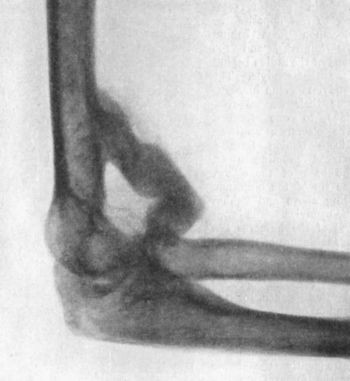

90 38.Radiogram of Incomplete Backward Dislocation of Elbow

91 39.Forward Dislocation of Elbow, with Fracture of Olecranon